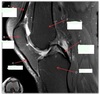

How well did you know this?

1

Not at all

2

3

4